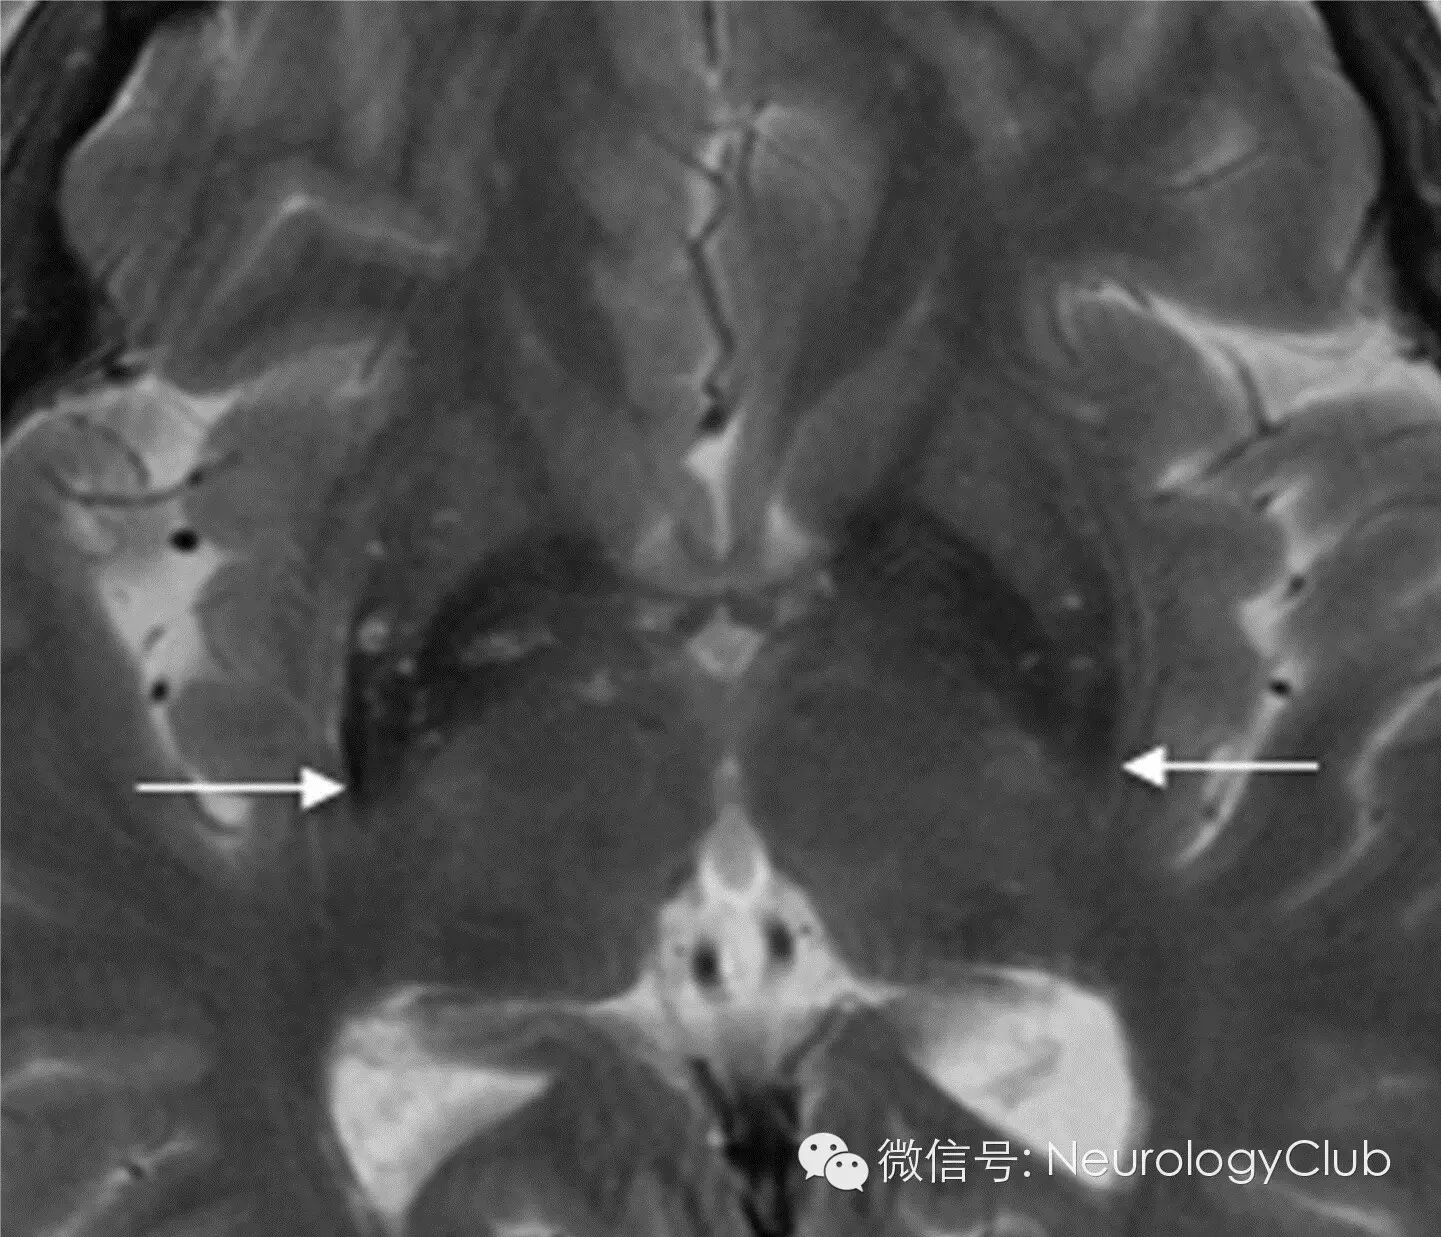

十字面包征(简称“十字征”,Hot cross bun sign)

MSA-C的MRI影像学表现包括橄榄、桥脑、小脑中脚和小脑的萎缩,横轴面上桥脑T2WI交叉样高信号,即所谓的“十字征”,是诊断MSA-C的较特征性的表现。“十字征”的病理学基础为桥脑核及其发出的通过小脑中脚到达小脑的纤维(桥横纤维)变性和神经胶质增生,T2WI信号增高,而锥体束和由齿状核发出的小脑上脚的纤维无变性,未出现异常信号。有学者认为,先出现“垂线征”,后出现“十字征”。“十字征”形成过程与桥脑小脑萎缩程度之间存在相关性,当“十字征”等级越高时,对应其桥脑面积越小。因此,根据MRI图像诊断MSA-C的敏感性和特异性非常高。然而,在脊髓小脑共济失调其他类型如SCA1、SCA2、SCA3以及继发于某种血管炎的帕金森征合并小脑、脑干功能障碍患者中,有相同的MRI影像学特点和组织学特点。

(脑桥“十字征”伴小脑萎缩